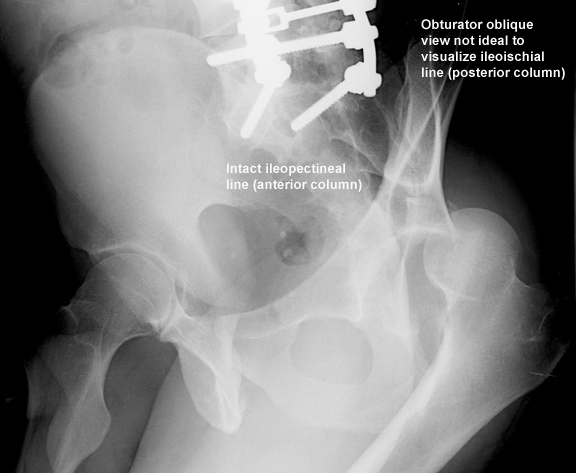

• judet

•  obturator oblique

• shows profile of obturator foramen

• shows anterior column and posterior wall

• Findings

• radiographic landmarks of the acetabulum

• iliopectineal line (anterior column)

• ilioischial line (posterior column)

• Percutaneous fixation with column screws

• posterior column screws

• imaging

• obturator oblique best view to rule out joint penetration

• inlet iliac oblique view best to determine anteroposterior position of screw within the pubic ramus

• obturator oblique inlet view best to determine position of a supraacetabular screw within tables of the ilium